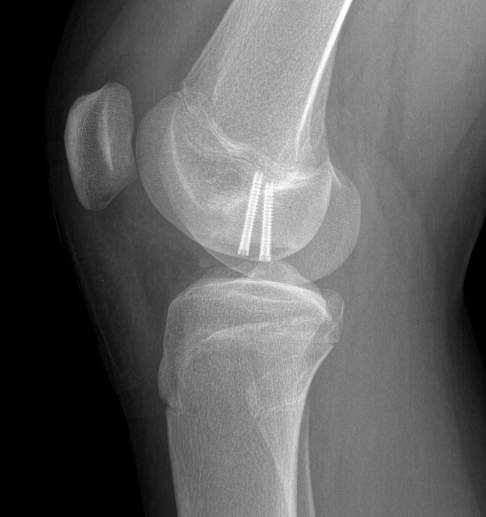

Inferior screw Superior screw

- typically 2 - 3 screws maximum (3.5 mm)

- 22 - 26 mm long, want to stop short of growth plate

- ensure screw heads are buried under cartilage, but not too deep so they still engage fragment